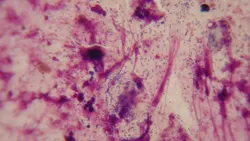

Increased numbers of bacteria in the presence of neutrophils suggest bacterial infection. Pseudomonas appears as rod-shaped organisms (Figure 3); if rods are identified, a second swab should be taken from the same site for submission for culture and sensitivity due to the potential for resistant bacteria. If otitis media is present, an additional sample should be taken from the middle ear because the susceptibility pattern of organisms from the 2 locations can be different.3

Featured Image

FIGURE 3

Cytology from ear with Pseudomonas infection